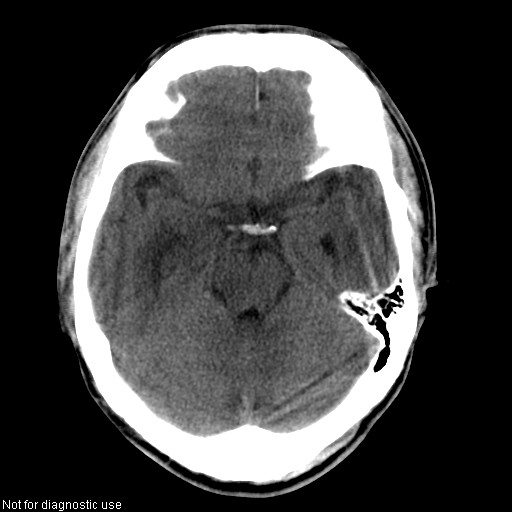

以下是引用hhcckk在2008-1-26 16:03:00的发言:[br]考虑病毒感染可能性大[br]1、病人发病时间短,1周,转移病灶时间长[br]2、楼主虽然没有告诉我们年龄,但从颅内情况来看,病人年纪不会很大,脑池,脑沟不是很明显,当然,可能有脑肿胀的原因,转移灶病人年纪一般较大[br]3、从病灶特点来看,转移多发生在灰白质交界区,多有指状水肿,占位效应明显,此病人呈对称性发布,发生在脑实质深部,与转移有所区别[br]4、病人经抗炎,止咳效果不好,可能是病毒感染,抗生素治疗效果不好[br]5、建议楼主1、增强 2、有呼吸系统的症状何不拍个胸片